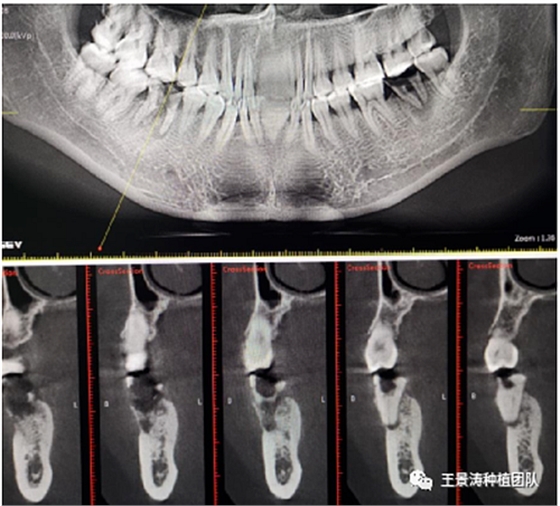

左側(cè)下頜第二磨牙及右側(cè)下頜第一磨牙同時(shí)即刻種植病例?;颊吣贻p女性,無系統(tǒng)性疾病。37及46殘冠及殘根,且46劈裂,無法冠修復(fù),必須拔除。37根尖慢性炎癥,大量肉芽組織存在,46根分叉較高,根分叉骨質(zhì)尚可。CBCT示:根尖骨質(zhì)至下牙槽神經(jīng)管距離可滿足種植體的初期穩(wěn)定性,遂考慮即刻種植,并在種植體周邊填入骨粉并覆蓋骨膜,雙側(cè)的種植體初期穩(wěn)定性相差無幾,但考慮到37根尖慢性炎癥較大,遂給予埋入式種植。